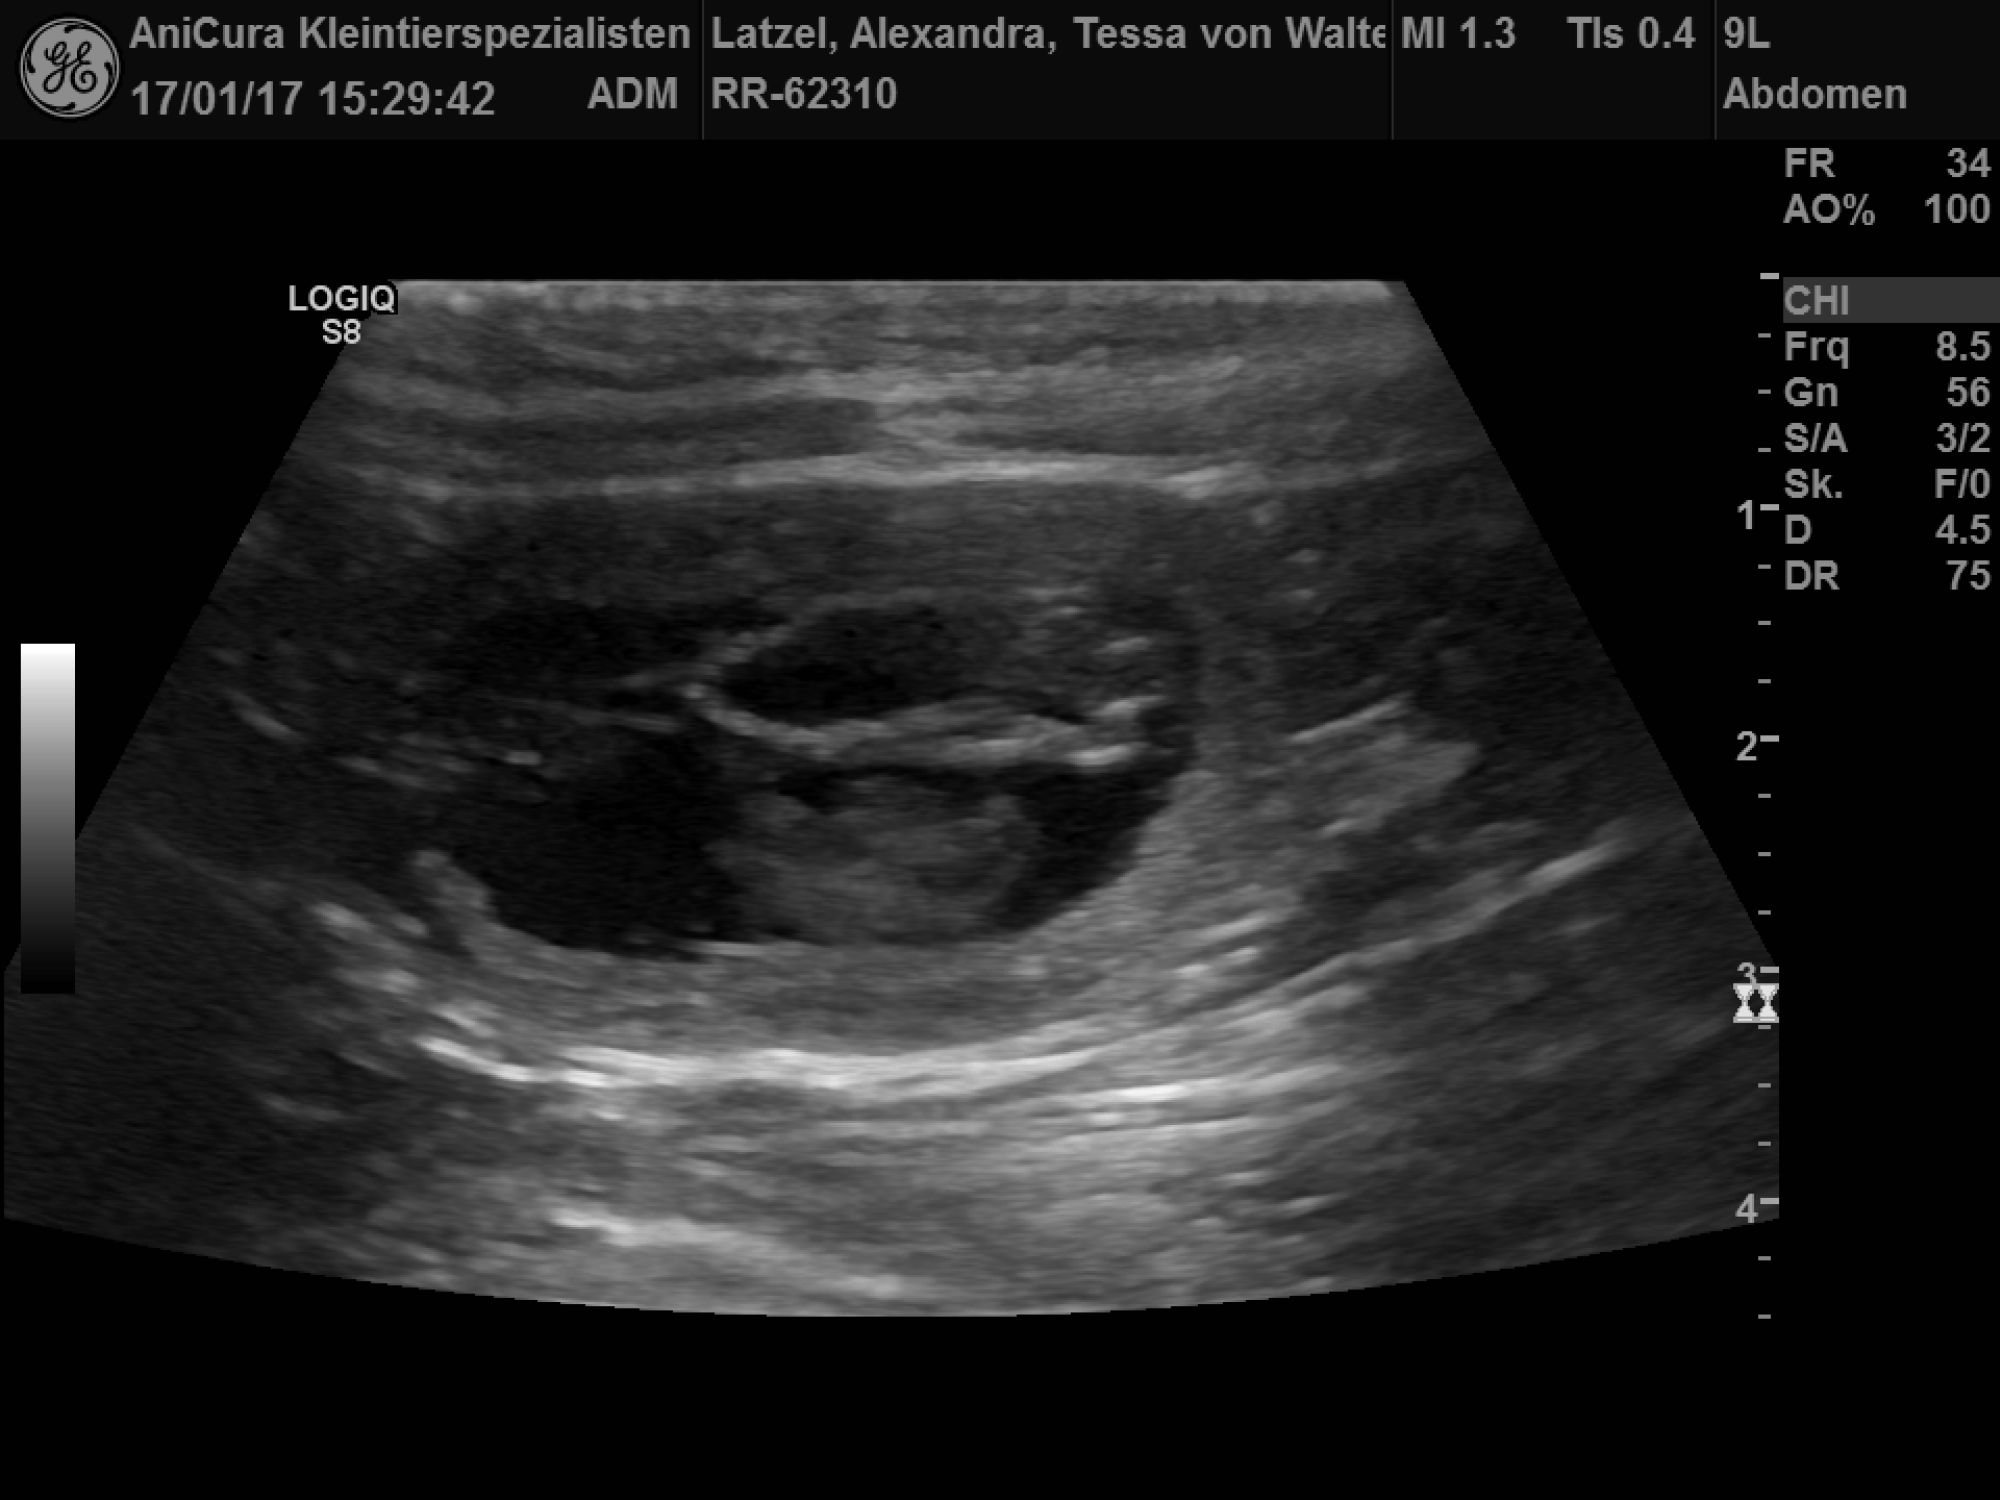

| Tessa ist Schwanger! Die Ultraschallbilder beweisen es! |

| Am 20.12.2016 war ich mit Tessa bei Spikey Brown genannt Finn zum Decken! |